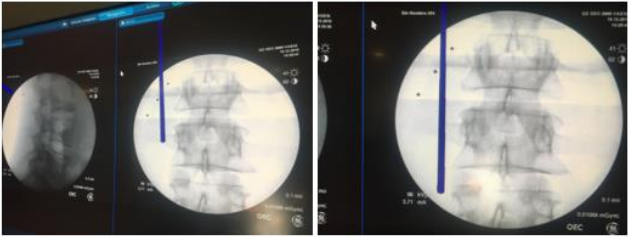

• Fluoroscopy or Neuronavigation Imaging: in our center we fused both, at the beginning of the procedure, during and after decompression, fluoroscopy or further endoscopic visualization is performed to ensure complete removal of the herniated disc material and adequate decompression of the nerve root (Figure 2).

Figure 2: fluoroscopy and neuronavigation fused. Identify the landmarks, superior transverse process (left image), inferior transverse process (right image).